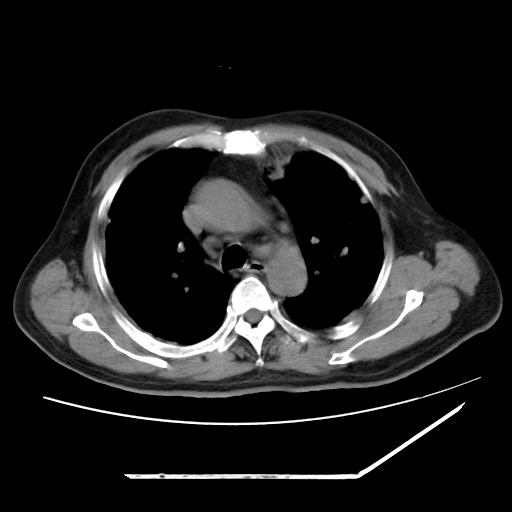

男,57,畏寒,发热

两肺野多发大小不一高密度灶,纵膈内见肿大淋巴结,要考虑转移瘤可能。双侧胸腔少量积液。

双肺多发结节样病灶,部分内见透光区,纵隔内见淋巴结肿大。结核临床如有畏寒,高热,白细胞增高首先考虑迁徙性肺脓肿(多是金黄色葡萄球菌感染)。

注意除外转移瘤。

1)考虑两肺感染性病变(金黄色葡萄球菌肺炎?);建议抗炎治疗后复查排除其他。2)双侧少量胸腔积液。